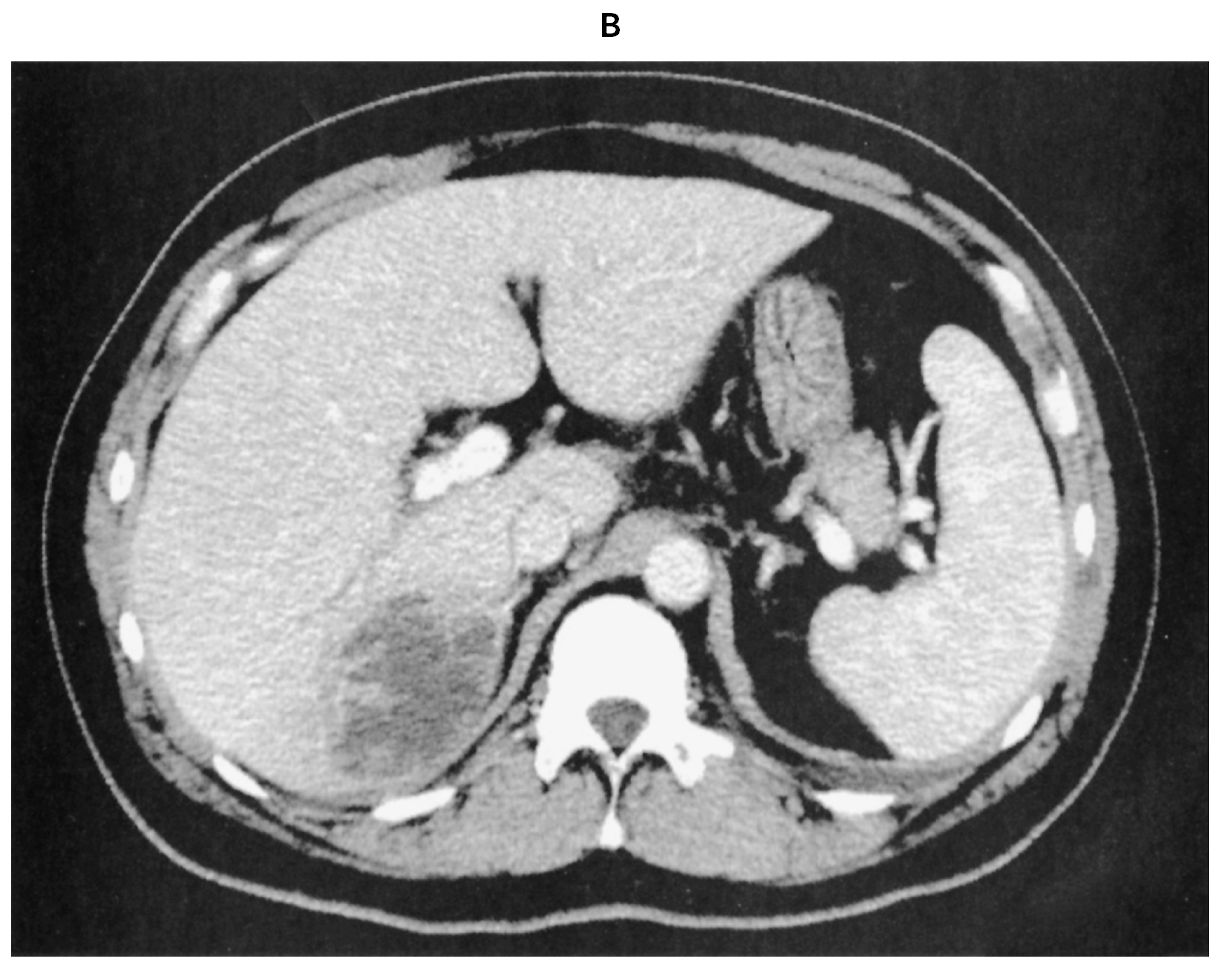

48歳の男性。悪寒と発熱を主訴に来院した。5日前から夕方になると38℃前後の発熱を生じ,軟便が続いていた。本日,悪寒を伴う発熱と両眼の視力低下を認めたため受診した。糖尿病で投薬治療中である。意識は清明。体温38.5℃。脈拍96/分,整。血圧140/74mmHg。呼吸数24/分。SpO2 97%(room air)。眼瞼結膜に異常を認めないが,両側の眼球結膜に充血を認める。頸部リンパ節を触知しない。心音と呼吸音とに異常を認めない。腹部は平坦で,右上腹部に圧痛を認める。右肋骨弓下に肝を3cm触知する。筋性防御と反跳痛は認めない。尿所見:蛋白(-),糖3+,ケトン体(-),潜血(-),沈渣に異常を認めない。血液所見:赤血球450万,Hb 14.0g/dL,Ht 45%,白血球14,600(桿状核好中球30%,分葉核好中球51%,好酸球1%,好塩基球1%,単球5%,リンパ球12%),血小板21万。血液生化学所見:総蛋白7.0g/dL,アルブミン3.5g/dL,総ビリルビン2.0mg/dL,直接ビリルビン1.5mg/dL,AST 35U/L,ALT 35U/L,LD 259U/L(基準124~222),ALP 220U/L(基準38~113),γ-GT 132U/L(基準13~64),アミラーゼ45U/L(基準44~132),CK 157U/L(基準59~248),尿素窒素19mg/dL,クレアチニン1.0mg/dL,尿酸7.2mg/dL,血糖198mg/dL,HbA1c 6.3%(基準4.9~6.0)。CRP 21mg/dL。胸部エックス線写真に異常を認めない。腹部単純CT(A)と腹部造影CT(B)とを下に示す。